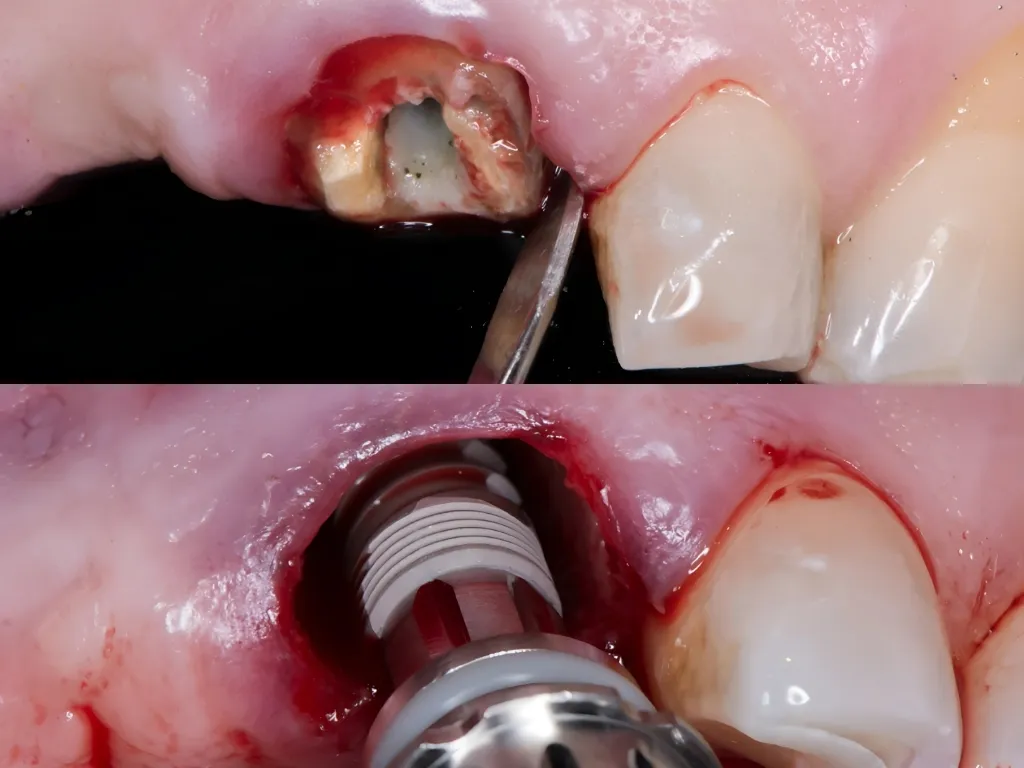

vaka_img

Soket Koruma ile Immediate Yükleme

Dr. Manuel de la Rosa

Immediate Geçici Protez Yüklemesi